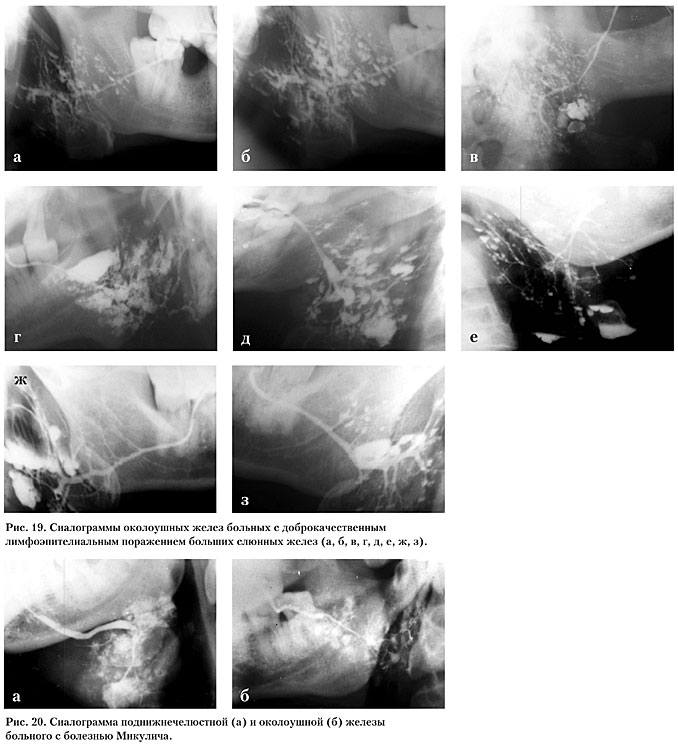

Сиалограмма при болезни Микулича